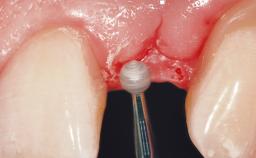

Immediate Flapless Placement of an Implant in a Maxillary Left Central Incisor Site

A 29-year-old female patient presented for treatment to replace the upper left central incisor tooth with an implant- supported restoration. The tooth had been intermittently symptomatic for the previous 12 months. The tooth had originally suffered trauma about 15 years previously. Several endodontic treatments had been performed, including an apicectomy procedure to retain the tooth. The patient was healthy and a non-smoker. She had reasonable expectations in regard to esthetic outcomes and the risk of marginal tissue recession following treatment. At medium smile, the gingival margins of the upper teeth were visible, with a display of 3 to 4 mm of the gingival margins. Gingival recession of tooth 21 and a discrepancy in the gingival levels between teeth 11 and 21 was observable during normal speech and smile.